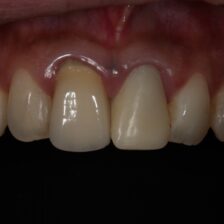

ダイレクトボンディングなどの

審美治療も高精度に対応

肉眼では見えない細かな部分まで拡大して確認できるため、削りすぎを防ぎ、再発リスクを抑えた質の高い治療が可能です。

当院では、カリーナシステムを活用し、治療前・治療中・治療後の状態を静止画や動画で記録。実際の映像を一緒に見ながら、分かりやすく丁寧にご説明します。

写真・動画で「見える説明」

治療前・中・後の丁寧な説明